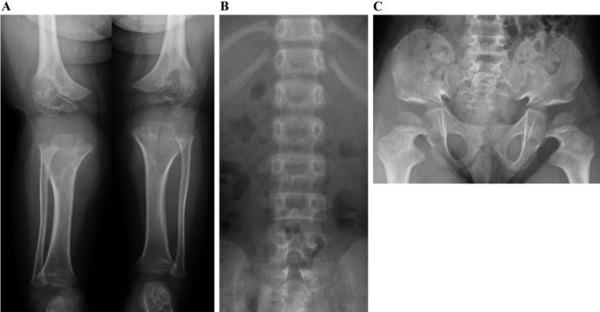

აქონდროპლაზიის მქონე ბავშვის ქვედა კიდურების, ხერხემლისა და მენჯის რენტგენი; წყარო - იაპონელი ექიმების აკადემიური რჩევები აქონდროპლაზიის მართვაზე - Clinical Practice Guidelines for Achondroplasia